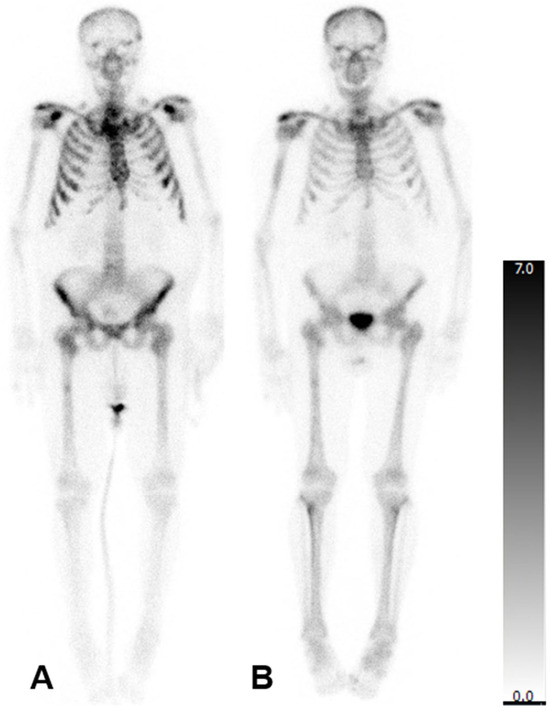

Log rank test showed no significant difference for patients undergoing six cycles of therapy when investigating the OS for patients with an aBSI above the mean of 2.6% and ≤2.6% (median OS > 2.6%: 431 days; median OS ≤ 2.6% 814 days; χ2 = 1.823, p = 0.177).

There was also no significant difference for patients undergoing three cycles of therapy when investigating the OS for patients with an aBSI above the mean of 4.5% and ≤4.5% (median OS > 4.5%: 129 days; median OS ≤ 4.5% 475 days; χ2 = 0.308, p = 0.579; Figure 3).

Figure 3. Kaplan–Meier curves comparing the overall survival (OS) in patients stratified by baseline aBSI values above or below the group mean, following six (A) or three (B) cycles of 223Ra therapy. (A) Median OS > 2.6%: 431 days; median OS ≤ 2.6% 814 days; although a trend toward improved survival was observed in patients with a lower aBSI, this difference did not reach statistical significance (χ2 = 1.823, p = 0.177). (B) Median OS > 4.5%: 129 days; median OS ≤ 4.5% 475 days; however, this difference was also not statistically significant (χ2 = 0.308, p = 0.579).